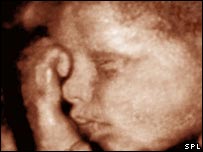

ब्रिटेन में रहने वाली भारतीय मूल की कई महिलाएँ सामाजिक दबाव में आकर कन्या भ्रूण हत्या के लिए भारत जाती हैं क्योंकि ब्रिटेन में ऐसा कर पाना उनके लिए संभव नहीं है. भारत में हालांकि अजन्मे शिशु के लड़का या लड़की होने की जानकारी देना कानूनन अपराध है लेकिन संयुक्त राष्ट्र के आँकड़ों के मुताबिक़ भारत में हर वर्ष साढ़े सात लाख कन्याओं को पैदा होने से पहले ही मार दिया जाता है. ऐसी ही एक महिला मीना (पहचान छिपाने के लिए नाम बदल दिया गया है) से बीबीसी संवाददाता संजीव भुट्टो ने बात की. मीना की कहानी उसी की ज़ुबानी. मेरा जन्म यूके में ही हुआ है और मैं एक पंजाबी मध्यवर्गीय परिवार में पली-बढ़ी हूँ. मैं उम्र तीस वर्ष है और मेरी तीन बेटियाँ हैं, मेरे ऊपर बहुत दबाव रहा है कि मैं बेटा पैदा करने में नाकाम रही हूँ. लड़का पैदा करने का सामाजिक दबाव भारतीय परिवेश में बहुत अधिक होता है और यह दबाव ब्रिटेन में रहने वाली महिलाओं पर भी कम नहीं होता. यह दबाव हमेशा पति के परिवार वालों की ओर से होता है. जैसे ही कोई महिला गर्भवती होती है, आसपास के लोग कहने लगते हैं, देखना लड़का ही होगा, हम लड़के पैदा होने पर खुशियाँ मनाएँगे लेकिन अगर लड़की पैदा हो जाए तो सब निराश हो जाते हैं. मन मसोस कर कहते हैं अच्छा चलो कोई बात नहीं.

आपको अपनी लड़की पर नाज़ होता है लेकिन लोग उससे ऐसे पेश आते हैं मानो वह किसी दुर्घटना का परिणाम हो, यह देखकर दिल बहुत दुखता है. जब मैं चौथी बार गर्भवती हुई तो मैंने और मेरे पति ने भारत जाकर पता करने का फ़ैसला किया है कि गर्भ में लड़का है या लड़की. हमें चिंता हो रही थी कि अगर इस बार लड़की हुई तो क्या होगा, यह परिवार के लिए बहुत ज़रूरी था और आर्थिक तौर पर भी हम चार लड़कियों का बोझ नहीं उठा सकते थे. मैंने इंटरनेट पर भारत के डॉक्टरों को खोजा, जब हमने उन्हें बताया कि हमारी तीन लड़कियाँ हैं और हम इस बार होने वाली संतान के बारे में पता करना चाहते हैं तो उन्होंने हमारी चिंता को समझा. दिल्ली में टेस्ट करवाने पर पता चल गया कि इस बार भी लड़की है और हमने उसे गिराने का फ़ैसला कर लिया. व्यक्तिगत तौर पर यह मेरे लिए बहुत ही दुखदायी फ़ैसला था, मैं नहीं चाहती थी कि मेरी बाक़ी बच्चियों को पता चले, मैं बहुत दुखी थे लेकिन मेरे पति काफ़ी संतुष्ट दिख रहे थे. मुझे पता था कि मैं सही नहीं कर रही हूँ इसलिए मुझे बुरा लग रहा था, सब कुछ बहुत ही बुरा था. ऐसा करने वाली मैं अकेली नहीं हूँ, कई महिलाओं ने ऐसा किया है लेकिन कोई इस बारे में बात नहीं करना चाहता.